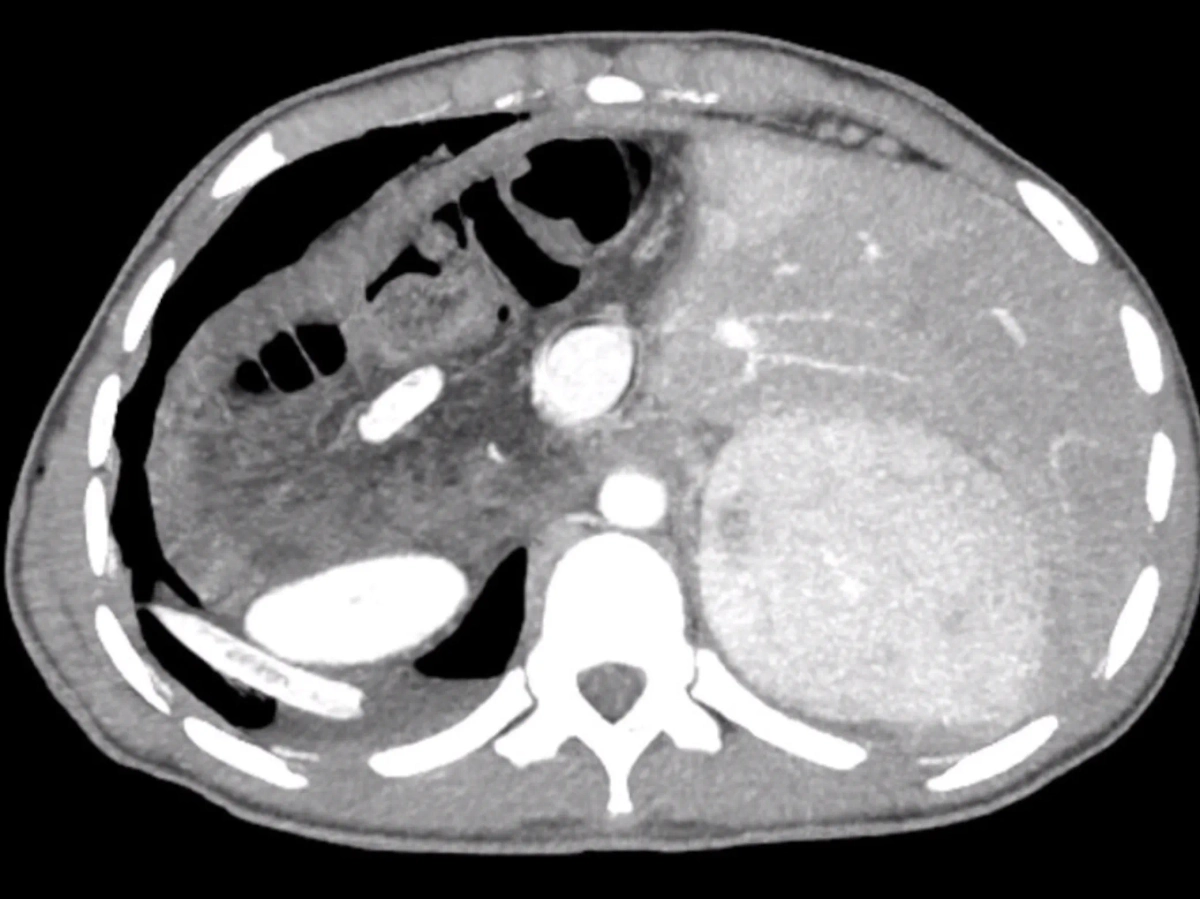

"Объёмное новообразование в печени молодого парня выявили во время УЗИ. Как оказалось, это гельминт альвеококк захватил печень и её магистральные сосуды. Он сумел прорасти в нижнюю полую вену, диафрагму и в правое лёгкое", — написал он в телеграм-канале.

3D-визуализация опухоли в печени нижегородца. Фото © Telegram / presseco